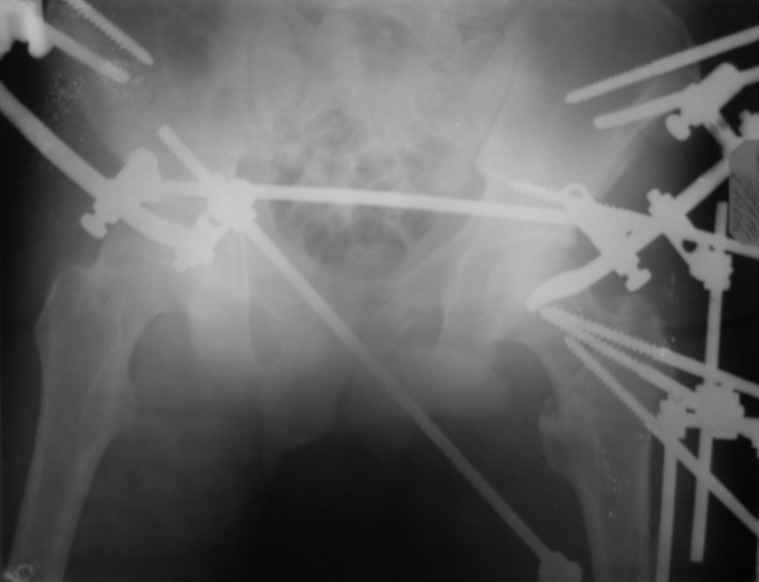

Вот снимки по свежей ситуации, парень 19 лет, длинный оскольчатый перелом бедра от шейки до в-с/3. давно уже ходит на своих ногах.

Представленные Вами рентгенограммы действительно являются примером качественной фиксации спице-стержневым аппаратом. Они, как ни что другое, многое иллюстрируют.

Кроме того, было бы ошибкой ставить знак равенства между нашим и Вашим пациентами. Они не только не похожи, разница между ними просто огромная. Говорю это не для того, чтобы задеть Вас или обидеть. Ни в коем случае. Просто теперь я понимаю, что Ваше мнением строится на простом преломлении Ваших подходов к лечению пациентов со свежими переломами, на ситуацию, абсолютно несопоставимую, подобную нашей.

Готов поспорить, не так уж огромна разница. Я вполне понимаю, что фиксация свежего отломка у 19-летнего парня и чего там осталось от головки-шейки-вертелов у вашего немолодого пациента - это не одно и то же. Но я продолжаю настаивать на том, что вы далеко не исчерпали возможности данного метода. А то, что вся ситуация происходит на фоне гнойной раны чуть ли не в самом очаге - вообще для меня делает непонятой дискуссию о выборе метода, метод выбора уже применяется, и даже успешно.

Если вернуться обратно к разнице - и там, и там главное что нужно пациенту после репозиции - качественная стабильная фиксация. Раз есть гной - значит, внеочаговая (так уж ортодоксально я обучен), и даже если существуют крутые технологии по погружному остеосинтезу на фоне гнойных проблем - тем не менее, зачем идти заведомо более сложным и затратным путём? Кроме того, зачем придумывать спейсер, когда вон какая мозоль и оссификаты, там есть чему срастись и так.

Компоновку данного аппарата, в котором дистальный отломок фиксирован лишь на дистальном уровне, а проксимальный вообще сам по себе никак, только через бывший сустав, назвать стабильной никак нельзя. Нет стабильности - нет нормального заживления, но есть осложнения, надеюсь, это-то можно экстраполировать на вашего больного?